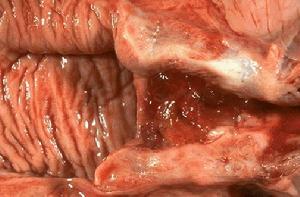

撤退性子宮出血儀器內視圖子宮內膜異位症,各種良惡性腫瘤,生殖系統器官性病變,有性生活者要注意流產。撤退性子宮出血治療青春期無排卵功血以促排卵,建立規律月經,避免復發為治則。更年期無排卵功血,則以遏制子宮內膜增生過長誘導絕經,防止癌變為重點。